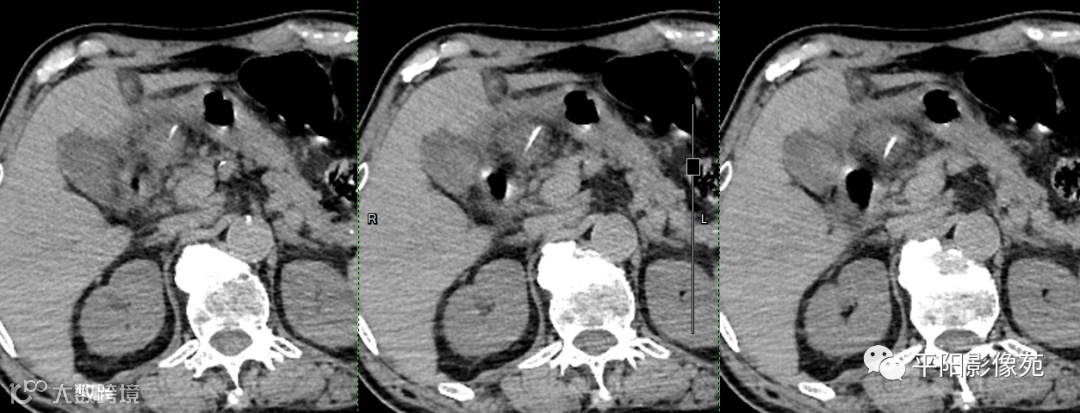

影像表现:

胃角胃壁增厚、毛糙,内侧可见一条状高密度,一端尖锐,周围可见软组织密度影包裹,边界不清。